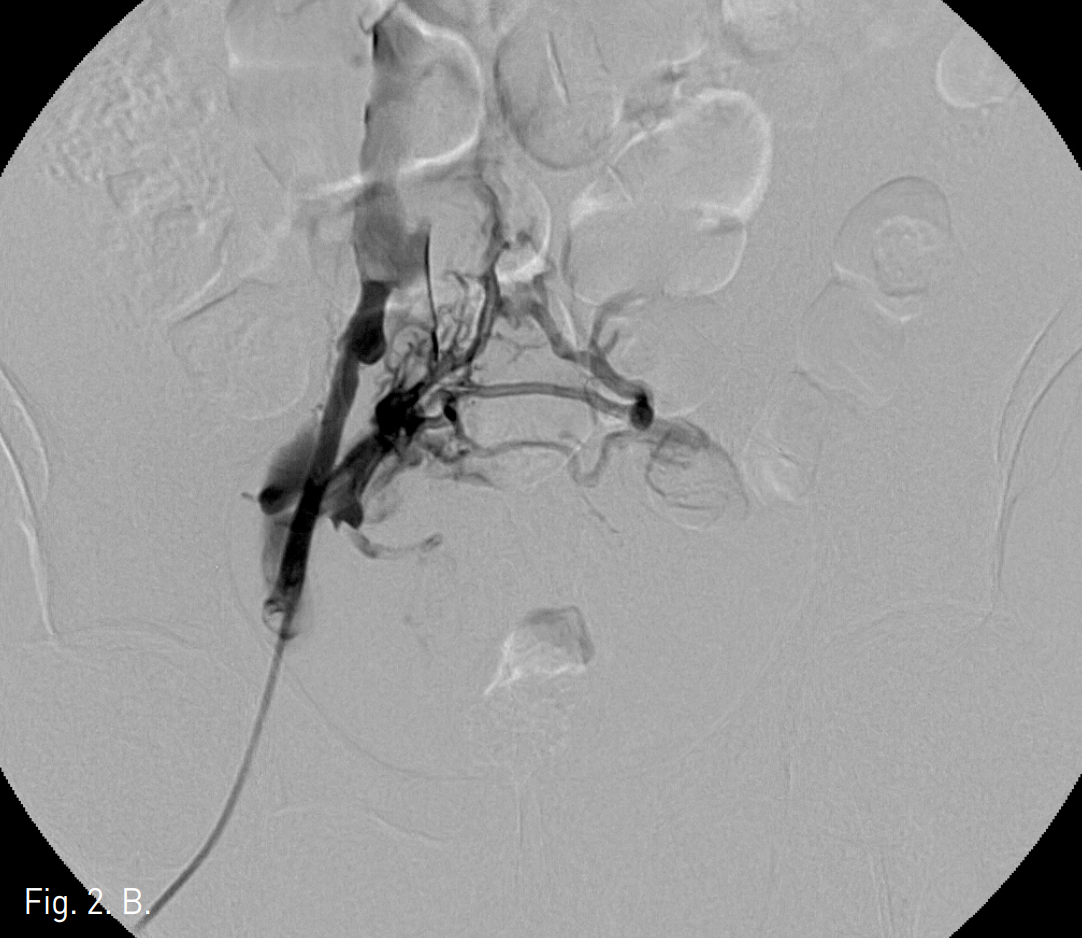

Fig. 2

Venograms obtained after contrast injection in the right (A) and left (B) iliac vein show thrombotic occlusion of both common iliac veins with collaterals.